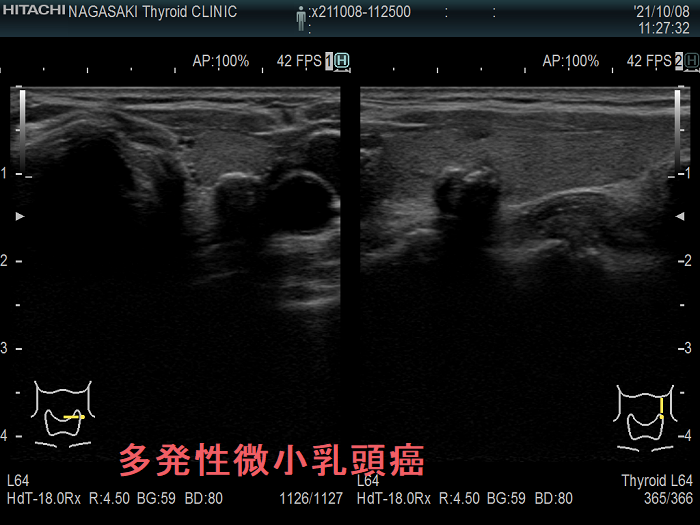

多発性の甲状腺微小乳頭癌

多発性の甲状腺微小乳頭癌は、リンパ節転移しやすいとされます(Am J Surg. 2014 Sep;208(3):412-8.)。

- 海外では、①両葉多発性の場合、②甲状腺癌の家族歴(遺伝性)がある場合、甲状腺微小乳頭癌であっても甲状腺全摘が推奨されます[アメリカ甲状腺学会(American Thyroid Association:ATA)やヨーロッパ分子癌学会(European Society of Molecular Oncology:SMO)のガイドライン](Thyroid. 2016 Jan;26(1):1-133.)(Ann Oncol. 2019 Dec 1;30(12):1856-1883.)(下記)